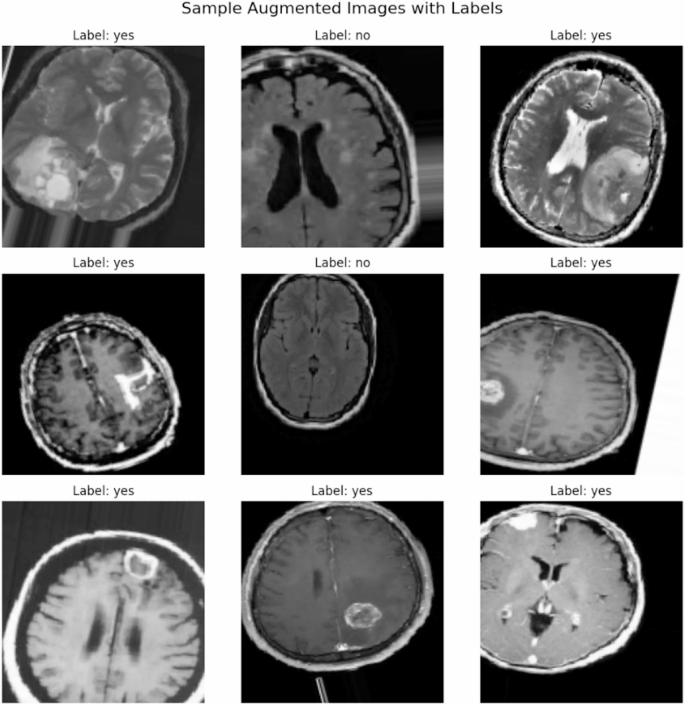

Figure 7 displays sample augmented images with their corresponding labels (“Tumour” or “No Tumour”). Data augmentation is performed using techniques such as random rotations, shifts, zooms, and flips. This step significantly increases the dataset’s diversity, enabling the deep learning model to generalize better by exposing it to varied scenarios during training.

Sample Augmented Images with Labels.